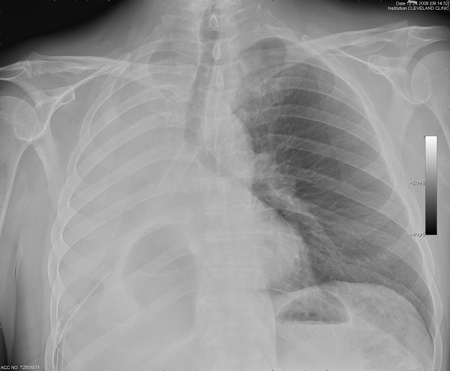

Central airway obstruction: malignant obstruction of the right mainstem

From the collections of Jose Fernando Santacruz MD, FCCP, DAABIP and Erik Folch MD, MSc; used with permission